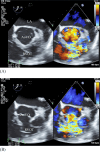

Ruptured sinus of Valsalva aneurysm (RSOVA) is a rare cardiac condition associated with high morbidity and mortality rates. We herein report a 35-year-old man with a history of ventricular septal defect (VSD). He had a history of interrupted hospital visits and presented to the emergency department with dyspnea, palpitations, and dizziness for a few days. Auscultation detected a continuous murmur. Transthoracic echocardiography followed by transesophageal echocardiography demonstrated RSOVA in the right ventricle with an aorto-right ventricular fistula. The fistula was resected, and the aneurysm was surgically repaired. The patient made a good recovery.